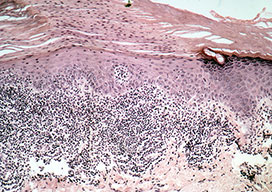

Arsenical keratoses = التقران الزرنيخي ARSENICAL KERATOSES Arsenical keratoses (ArKs) are precancerous lesions found in association with chronic arsenicism. These lesions have the potential to develop into invasive SCC. Arsenic is a ubiquitous element that has no color, taste, or odor. It has the potential to cause characteristic acute and chronic syndromes in persons exposed […]